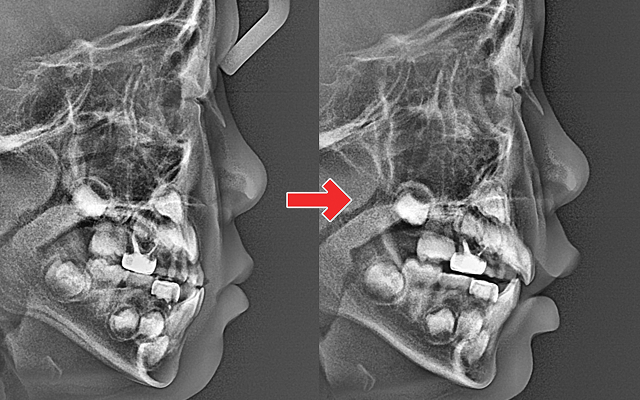

턱뼈의 성장이 비대칭으로 진행되어 성인 교정 시 수술이 필요할 수도 있음(양악수술)

교합 불균형으로 턱관절 통증, 비대칭 얼굴선이 생길 수 있음

- 디지털 스캔을 통해 성장 예측 기반으로 정밀한 설계